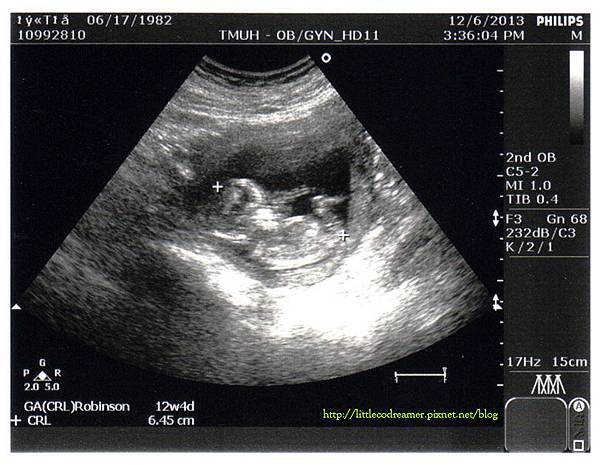

驗完血後,自費超音波也差不多輪到我了。由於覺得自己吐這麼慘,又如此食不下嚥,還是要看一下寶寶才安心。看到寶寶有正常長大讓我覺得非常欣慰,再怎麼用力吐都無所謂了。

↑寶寶四肢的雛形都看得出來了。目前應有天數為13W4D,超音波算出實際大小為12W4D,(誤差範圍約正負七日內)。身長已增至6.45CM。